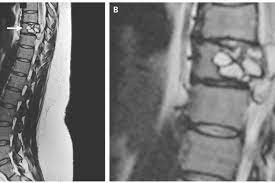

Dokter Temukan Cacing Pita Bersarang Di Tulang Belakang Perempuan Ini